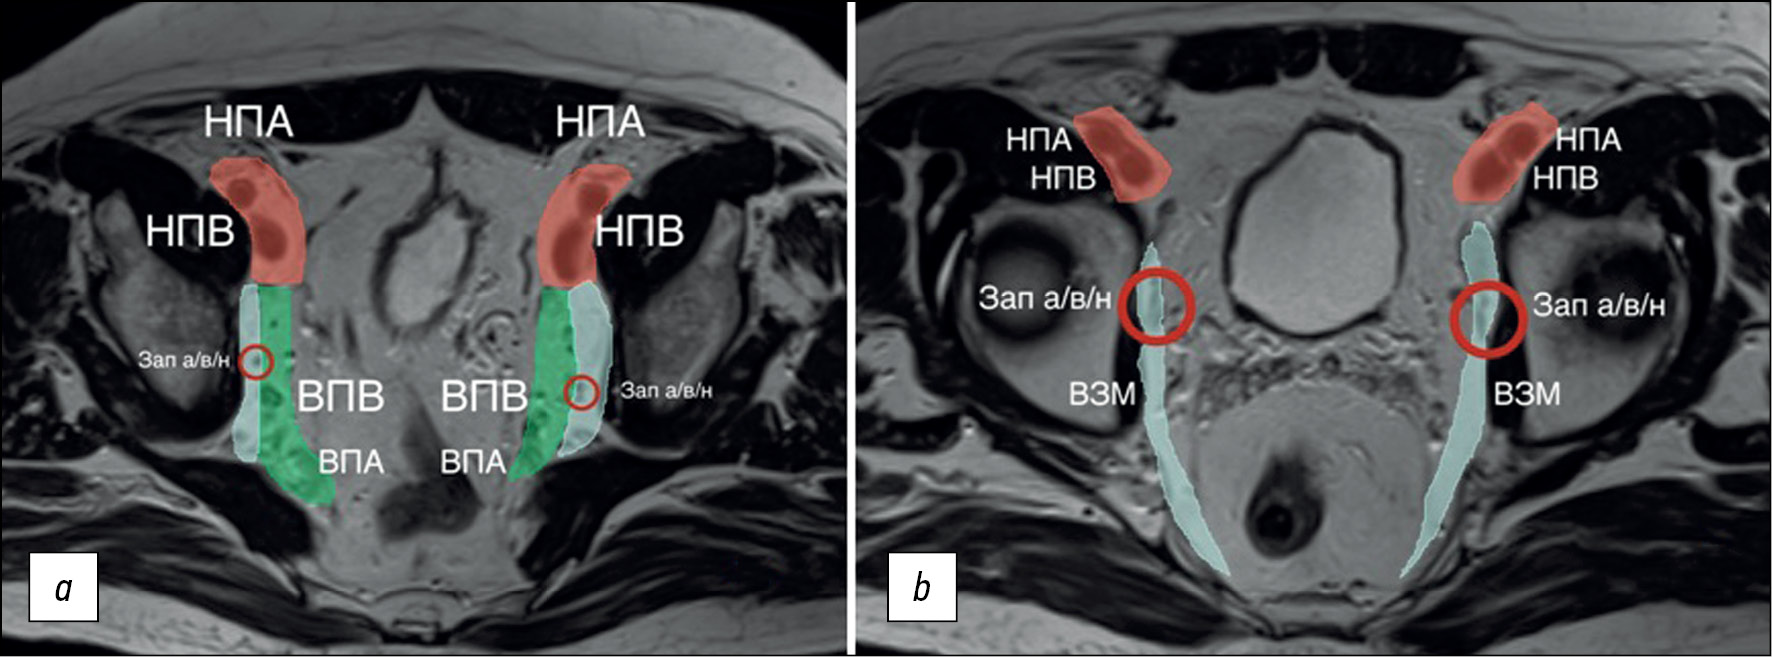

Not all lymph nodes located in the pelvis are regional for rectal cancer and are classified as “N.” When assessing pelvic lymph nodes as regional, it is important to consider their location (Fig. 4) and, if possible, indicate it in the examination report. Here are terms related to location, staging, and criteria for lymph node involvement.

The internal iliac lymph nodes are regional and, in the case of rectal cancer, are included in the scope of dissection of the lateral pelvic lymph nodes. They are located along the internal iliac vessels. At the level of the obturator muscle, they are localized medially to the internal iliac artery; lymph nodes lateral to the internal iliac artery are considered obturator lymph nodes (Fig. 4).

Fig. 4. Localization of the lateral pelvic lymph nodes (colored): external iliac lymph nodes are red; obturator lymph nodes are blue; and internal iliac lymph nodes are green. Shown in levels (a) proximal and (b) distal. EIA: external iliac artery; EIV: external iliac vein; IIV: internal iliac vein; IIA: internal iliac artery; Obt a/v/n: obturator artery/vein/nerve; OIM: obturator internus muscle.

The obturator lymph nodes are regional. They are located between the external and internal iliac arteries, medially to the internal obturator muscle and laterally to the internal iliac artery (Fig. 4).

The external iliac lymph nodes are not regional. They are located along the external iliac vessels (Fig. 4) and are divided into lateral, middle/median, and medial chains. The lateral subgroup is located laterally to the external iliac artery. The middle/median group is between the artery and the vein. The medial group is posterior to the external iliac vein. The lymph nodes in the medial subgroup are located near the obturator vessels and obturator lymph nodes. This can cause diagnostic difficulties because they are often indistinguishable from the obturator lymph nodes localized along the obturator artery at the point of its origin from the internal iliac (hypogastric) artery at the level of the internal obturator muscles [3]. Involvement of the external iliac lymph nodes in rectal cancer is extremely rare. Non-regional lymph nodes are considered suspicious if they measure >10 mm in short axis.